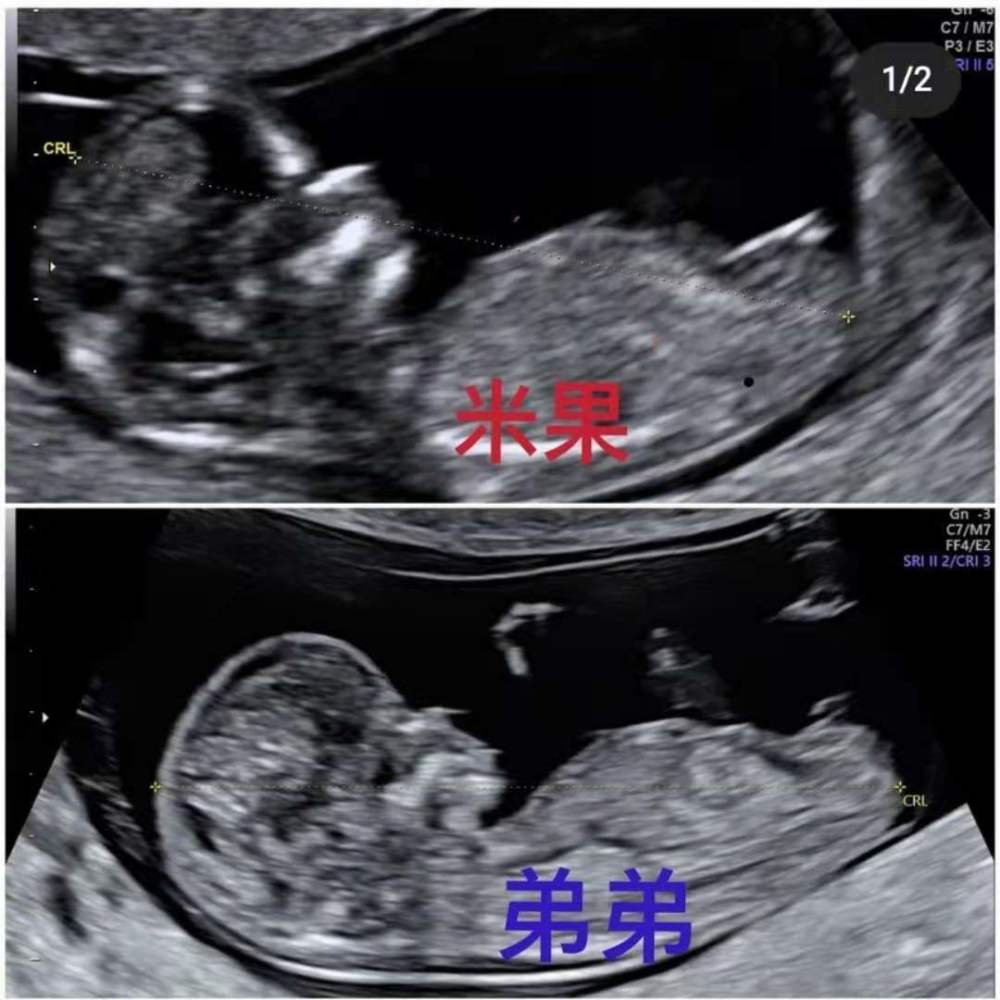

同时,她还晒出了一胎女儿米果和二胎男孩的B超照片,在评论区向网友们征集二胎男孩的名字,言语中难掩喜悦之情。